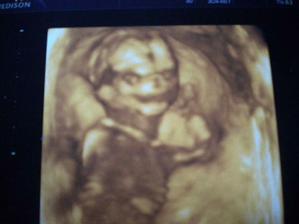

Kontrola proběhla v pořádku a mamka se zkusila zeptat, jestliuž nejde vidět o koho v břiše jde 😉 Pan doktor chvíli hledal, jednou to vypadalo na kluka, pak na holku, ale nakonec našel bezpečně to, co holčičky rozhodně nemají 😉 Takže jestli nejsme s panem Dr. úplně slepí, bude mít v prosinci Amelinka bráchu - Jáchyma...